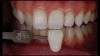

(18. and 19.) Tooth shade analysis of value, chroma, and hue taken with a smartphone and an EALS device.

Figure 18

Figure 19

Shade Selection and Laboratory Communication

The most utilized intraoral photographs in the field of dentistry are perhaps those that capture shade information (Figure 18 and Figure 19). The analysis of color (ie, value, chroma, hue) in dentistry is a critical step in the fabrication of esthetic indirect restorations, such as all-ceramic crowns and porcelain laminate veneers. The ability to properly communicate this information with the dental laboratory is essential to ensure an appropriate shade match, a reduction in chairtime and overhead, and most importantly, a satisfactory patient experience and treatment outcome. In recent years, the use of polarized light photography as an aid in the shade selection process has become extremely popular. For some EALS devices, special polarizing filters have been specifically designed to fit over the light-emitting portion of the device (Figure 20 and Figure 21). The images produced using polarized light photography demonstrate an elimination or reduction in the specular reflection of hard and soft tissue, resulting in a matte-finish appearance of the dentition and gingiva. These types of photographs aid the ceramist in identifying areas of opacity and translucency, crack lines, hypo- or hypercalcification, and other internal features of the dentition that may not be readily visible without such a filter (Figure 22).